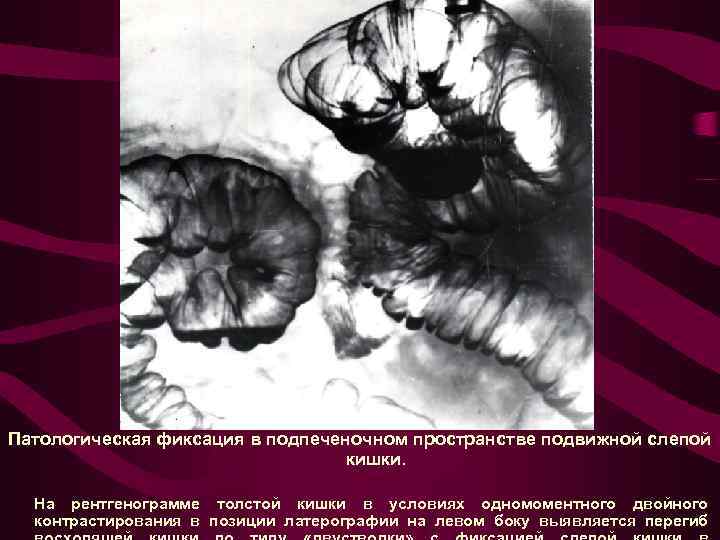

Патологическая фиксация в подпеченочном пространстве подвижной слепой кишки. На рентгенограмме толстой кишки в условиях одномоментного двойного контрастирования в позиции латерографии на левом боку выявляется перегиб